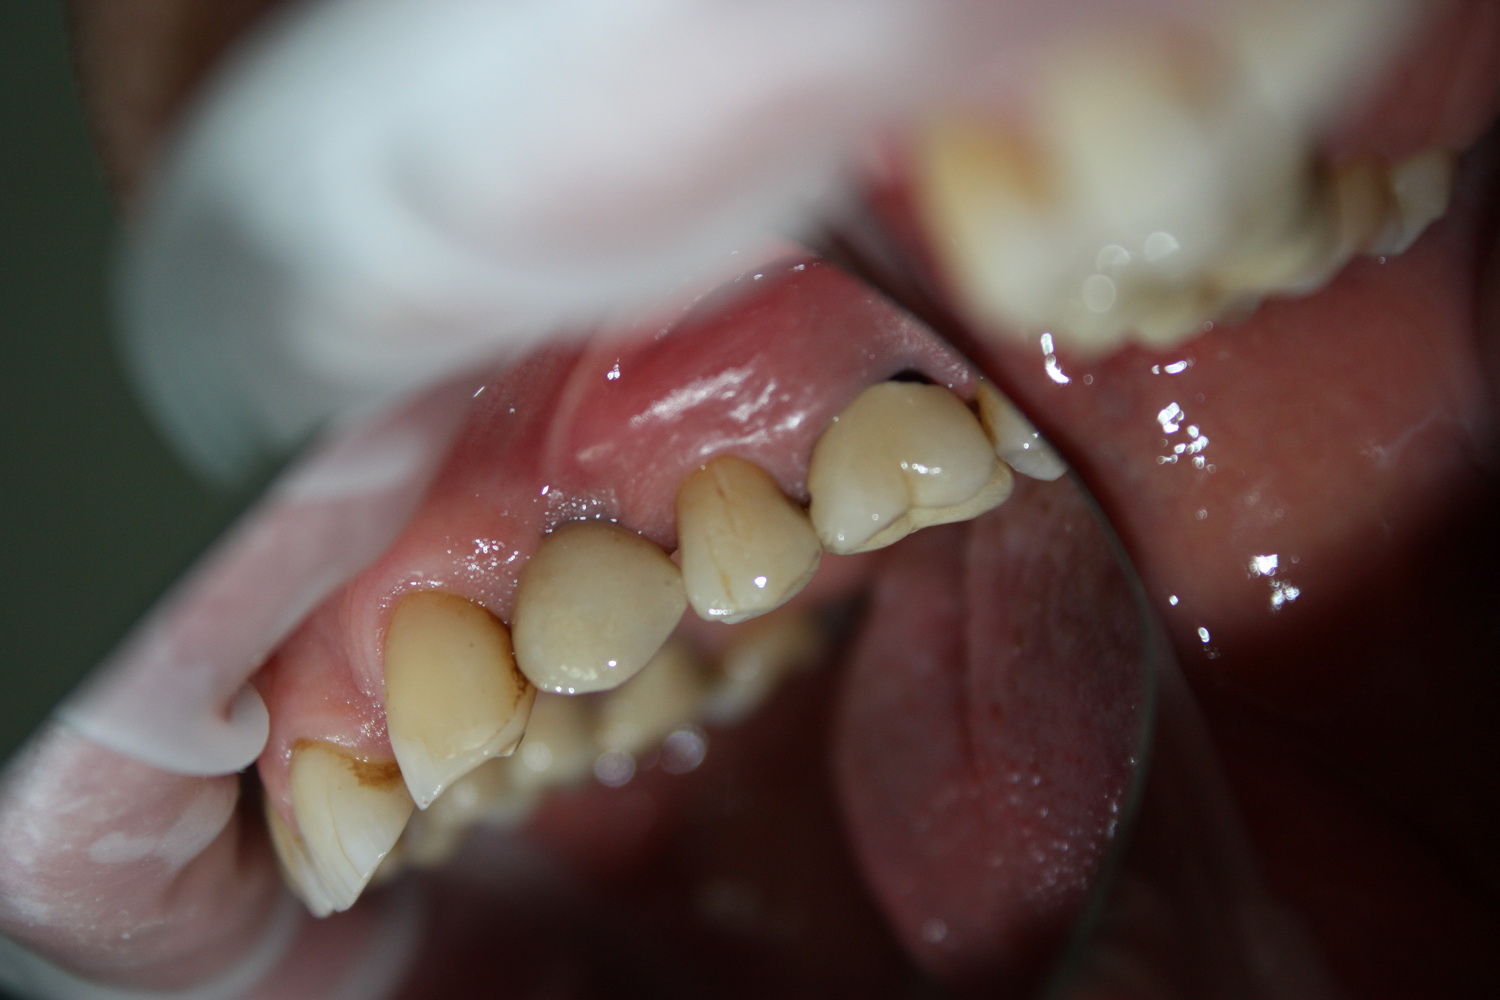

К счастью, уже через 6 недель после операции вдруг выяснилось, что ничего исправлять не нужно:

Фактически, нам осталось лишь дождаться приемлемого уровня остеоинтеграции имплантатов,  — примерно 2-3 месяца, — и можно переходить к постоянному протезированию.

Постоянные протетические конструкции

Через три месяца мы сняли коронки с имплантатов, чтобы оценить качество формирования десневого контура:

С этого момента можно перестать переживать — десневой контур сформировался правильно, мы получили достаточный объём и качество окружающей платформу имплантата десны. Можно приступать к изготовлению постоянной протетики. Подрядчиком стала зуботехническая лаборатория French Creative, одна из топовых лабораторий Москвы.